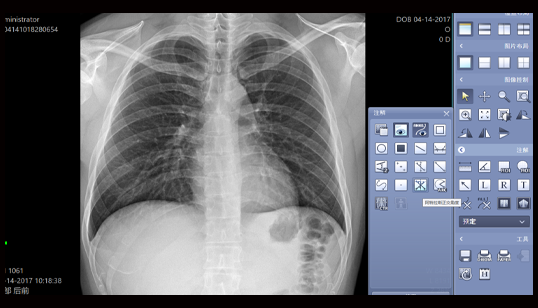

胸片不同尺寸对比

影像清晰,细节突出,无伪影